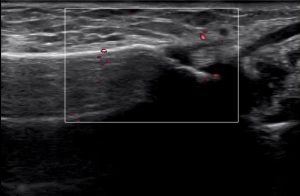

エコーで見ると・・・

背側(手の甲側)こんな感じです。